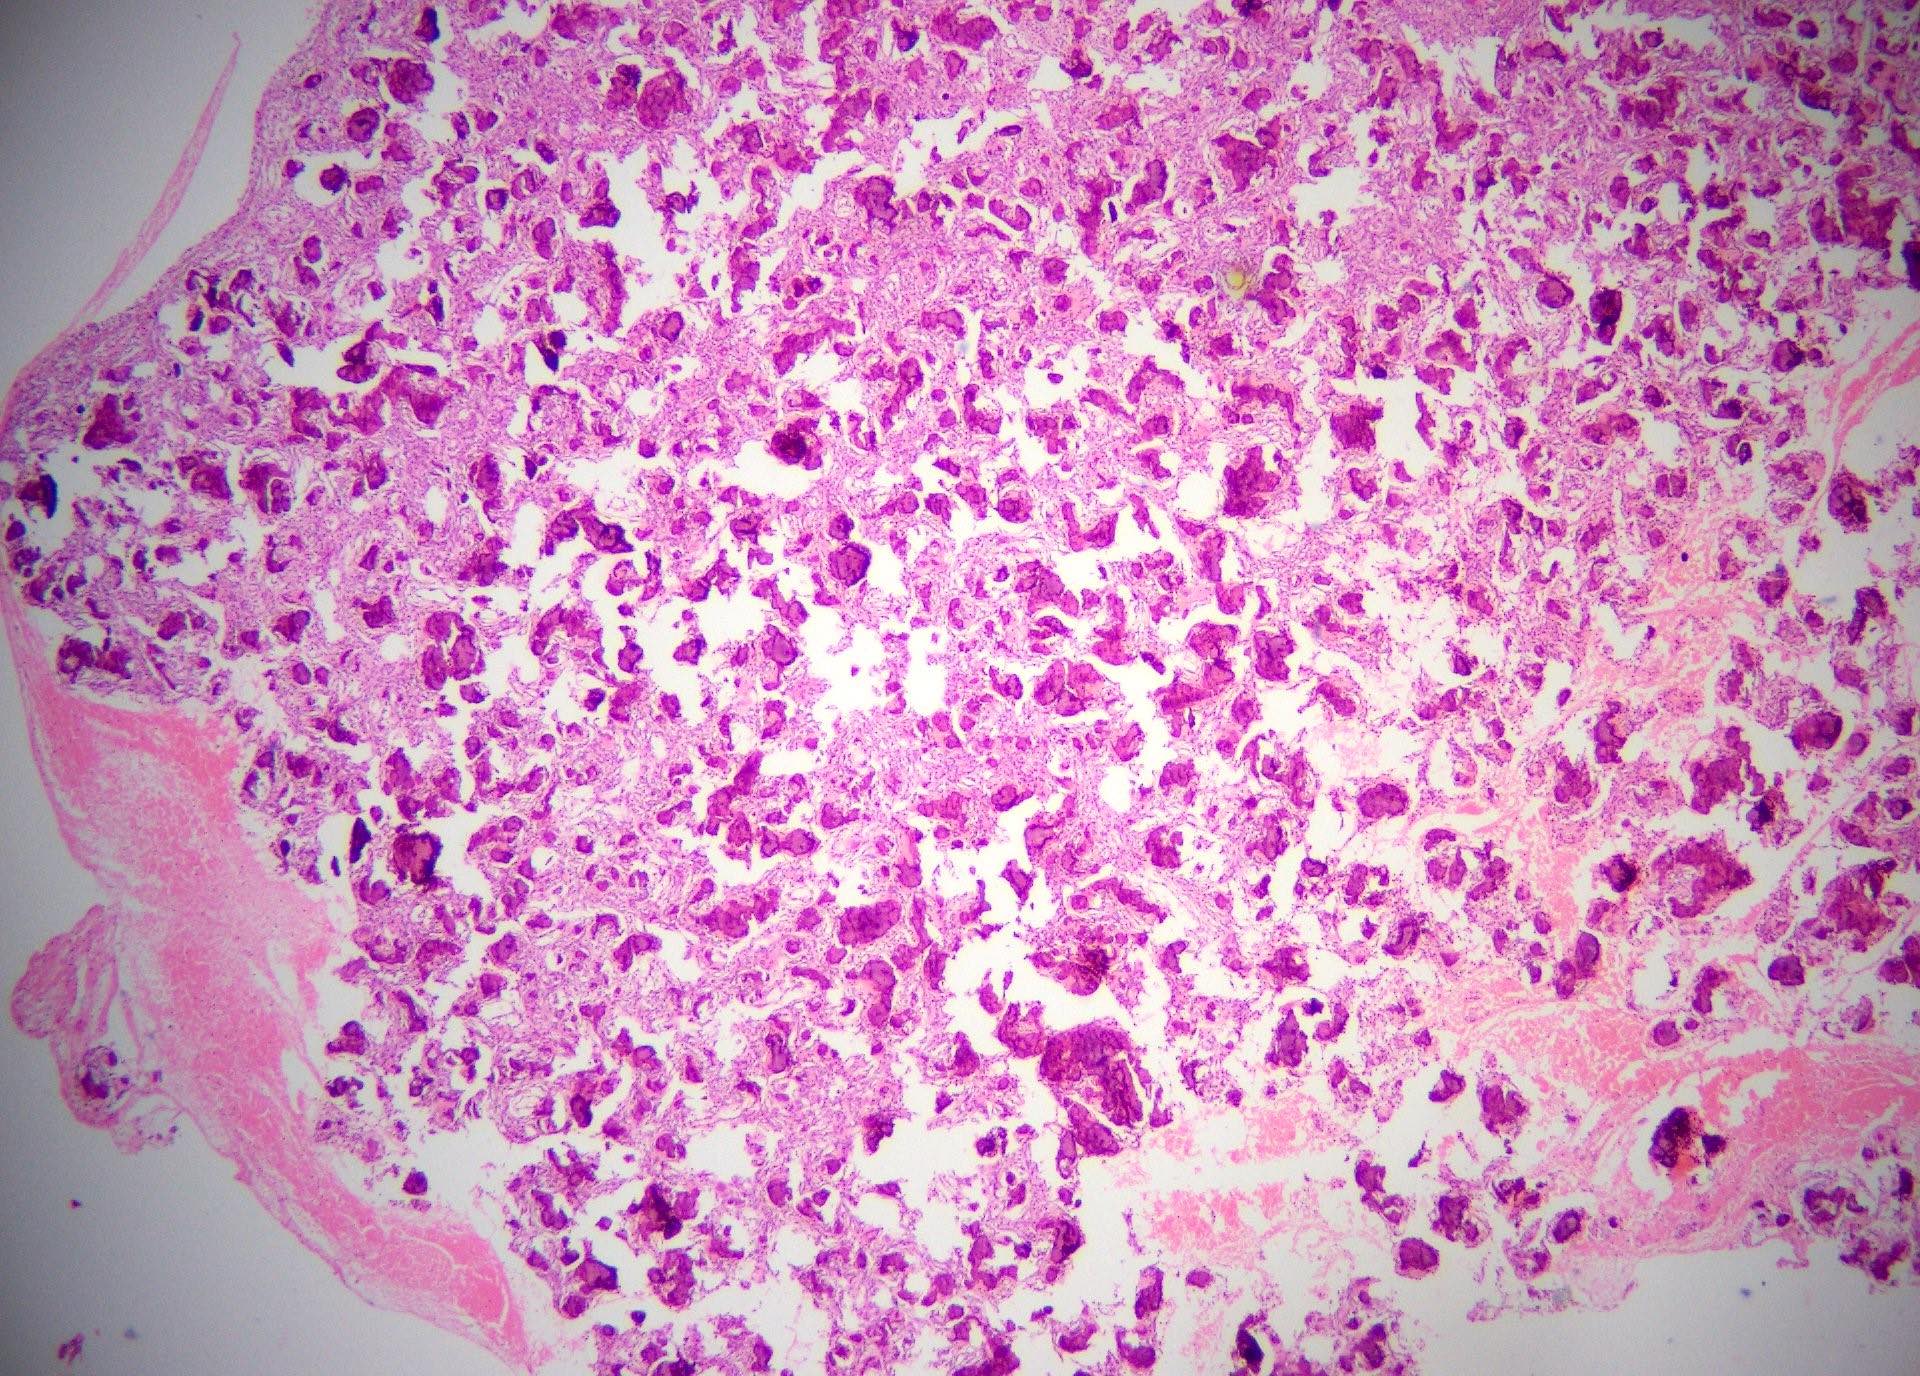

Microscopic (histologic) images

Contributed by Saira Javeed, M.B.B.S., M.Phil., Kelly Magliocca, D.D.S., M.P.H. and Molly Housley Smith, D.M.D.

- Well defined lesion; may have thin fibrous capsule

- Well demarcated margin from surrounding normal bone

- Lesion consists of variable proportion of fibrous and mineralized tissue, more heavily mineralized centrally; it shows variation in the amount and type of mineralization, even within a single lesion

- Osteoblastic rimming of bone trabeculae is frequent (J Stomatol Oral Maxillofac Surg 2022;123:364)

- Stroma is fibroblastic with areas of hypercellularity and nuclear hyperchromasia

- No significant atypia and mitoses are infrequent (Head Neck Pathol 2020;14:70)

- Woven to lamellar bone, osteoid and dense acellular or paucicellular basophilic rounded cementum-like calcifications may all be present (Head Neck Pathol 2020;14:70)

- Bony trabeculae may form thick anastomosing strands or fuse into large sheets centrally

- Hemorrhagic cystic degeneration, resembling aneurysmal bone cyst formation, is more often found in juvenile active ossifying fibromas but has been reported in rare COFs (J Stomatol Oral Maxillofac Surg 2022;123:364, Head Neck Pathol 2022;16:248)